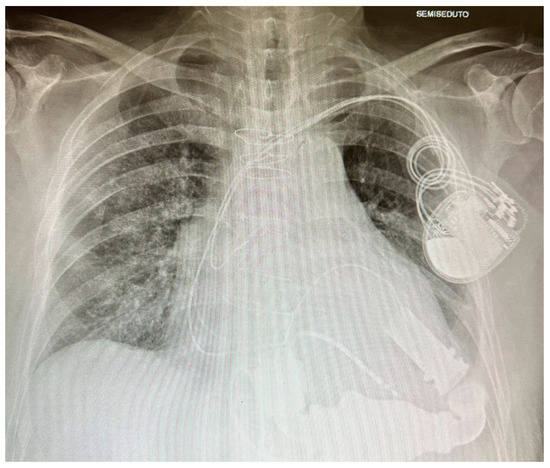

3. LVAD: A Machine to Supplement the Heart